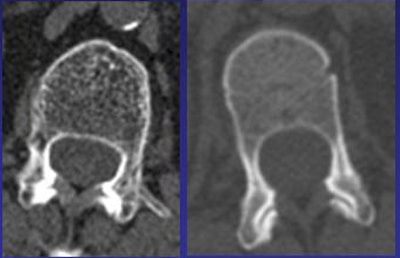

![]() |

| QCT images show osteoporotic L1 vertebral body (left, 55 mg/cc, CT attenuation 46 HU) compared to normal subject (right, 165 mg/cc, CT attenuation 207 HU). |